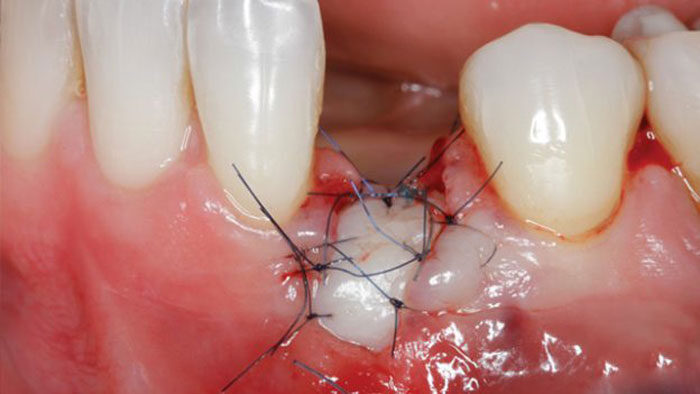

Extraction Socket – Preservation/Grafting; Immediate vs Delayed Implants; Pontic Site Development